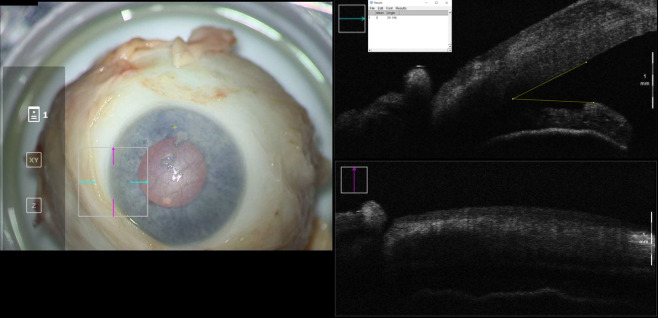

Introduction: During endothelial keratoplasty, anterior chamber gas is titrated to a desired fill, which is difficult to optimize by visualization alone. This study evaluates how an anterior chamber gas fill correlates with intraocular pressure (IOP) and iris-angle configuration as identified by optical coherence tomography (OCT).

Methods: Eleven cadaveric eyes were studied in three configurations: baseline, air-fill just spanning limbus-to-limbus ("full-fill"), and air-fill maximally filling the anterior chamber ("overfill"). At each configuration, IOP was measured by Tonopen and iris-angle was determined by analyzing OCT images.

Results: No differences in IOP or irisangles were identified between baseline and full-fill configurations (p=0.113 and p=0.152, respectively). When compared to overfill configuration, differences in IOP and iris-angles were identified for baseline (p<0.001 and p=0.001, respectively) and full-fill configuration (p=0.001 and p=0.039, respectively).

Discussion: These findings highlight that en-face visualization of full-fill may not be indicative of IOP elevation. A significant difference in IOP and iris-angle exists between full-fill and overfill configurations. Intraoperative OCT can serve as a useful surrogate to identify the extent of fill.